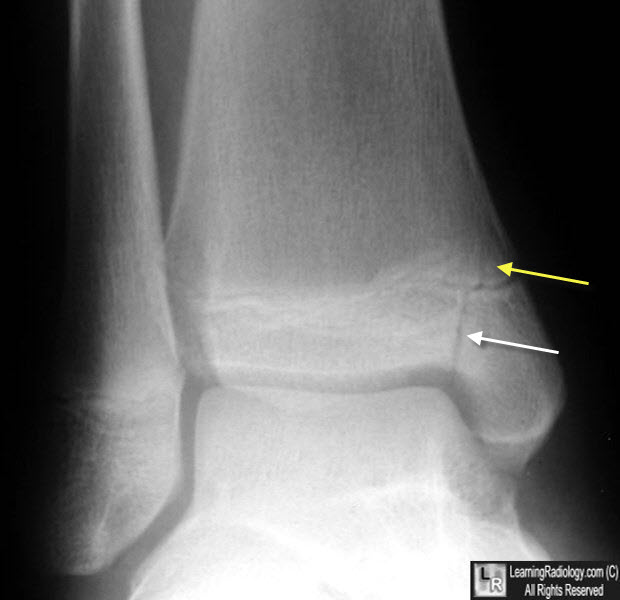

The Salter-Harris classification system is a widely used framework for categorizing physeal fractures in children, which are injuries that affect the growth plates of bones. Among the five types of Salter-Harris fractures, Type 2 is the most common, accounting for approximately 75% of all physeal fractures. A Salter-Harris Type 2 fracture involves a fracture through the growth plate and the metaphysis, which is the wider part of the bone adjacent to the growth plate. This type of fracture is characterized by a disruption of the growth plate and a break in the metaphyseal bone, but the epiphysis (the rounded end of the bone) remains intact.

A Salter-Harris Type 2 fracture typically presents with pain, swelling, and limited mobility in the affected limb. The fracture may be caused by a variety of mechanisms, including bending, twisting, or compression forces. In some cases, the fracture may be accompanied by a displacement of the bone fragments, which can lead to an obvious deformity. The diagnosis of a Salter-Harris Type 2 fracture is usually made based on a combination of clinical evaluation, radiographic imaging (such as X-rays), and, in some cases, advanced imaging modalities like CT or MRI scans. It is crucial to accurately diagnose and treat these fractures to prevent potential long-term complications, such as growth disturbances or limb length discrepancies.